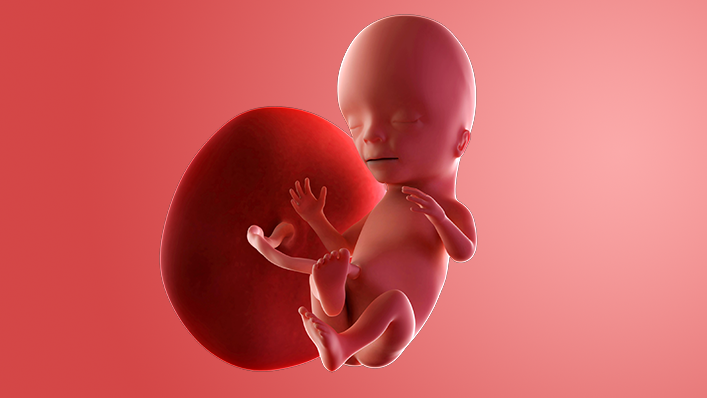

What does my baby look like?

Your baby, or foetus, is around 7.4cm long, which is about the size of a peach.

Your baby's ovaries or testes are fully developed inside and final tweaks are being made on the outside.

The baby is moving around. At first the movements are very jerky and random but then they start to look more deliberate. You may not feel any movement until around week 17.

Some babies suck their thumb in the womb. This actually serves a purpose as it helps to develop their sucking reflex. They'll need this when it comes to feeding.